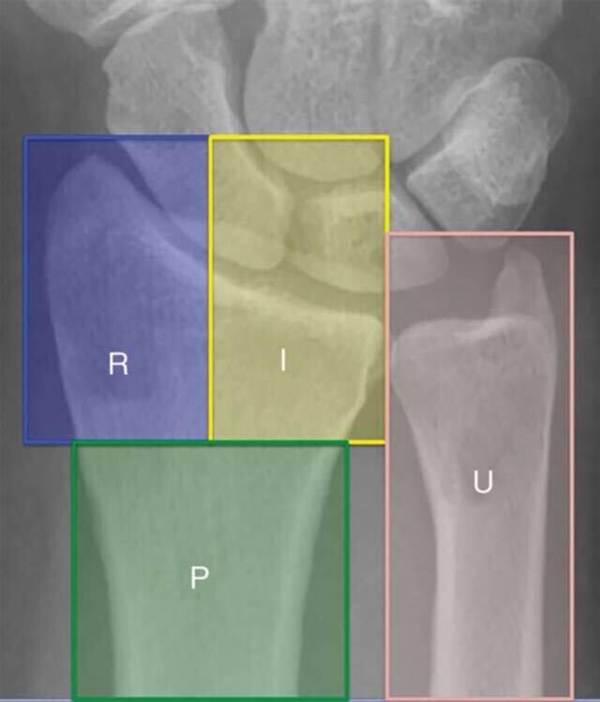

尺桡骨远端功能上分为三柱;

桡骨远端包含桡侧柱及中柱;

尺骨远端和三角纤维软骨复合体构成尺侧柱。

图1 前后位X线显示尺桡骨远端三柱结构,R为桡侧柱,I为中柱,U为尺侧柱,P为桡骨远端基底干骺端